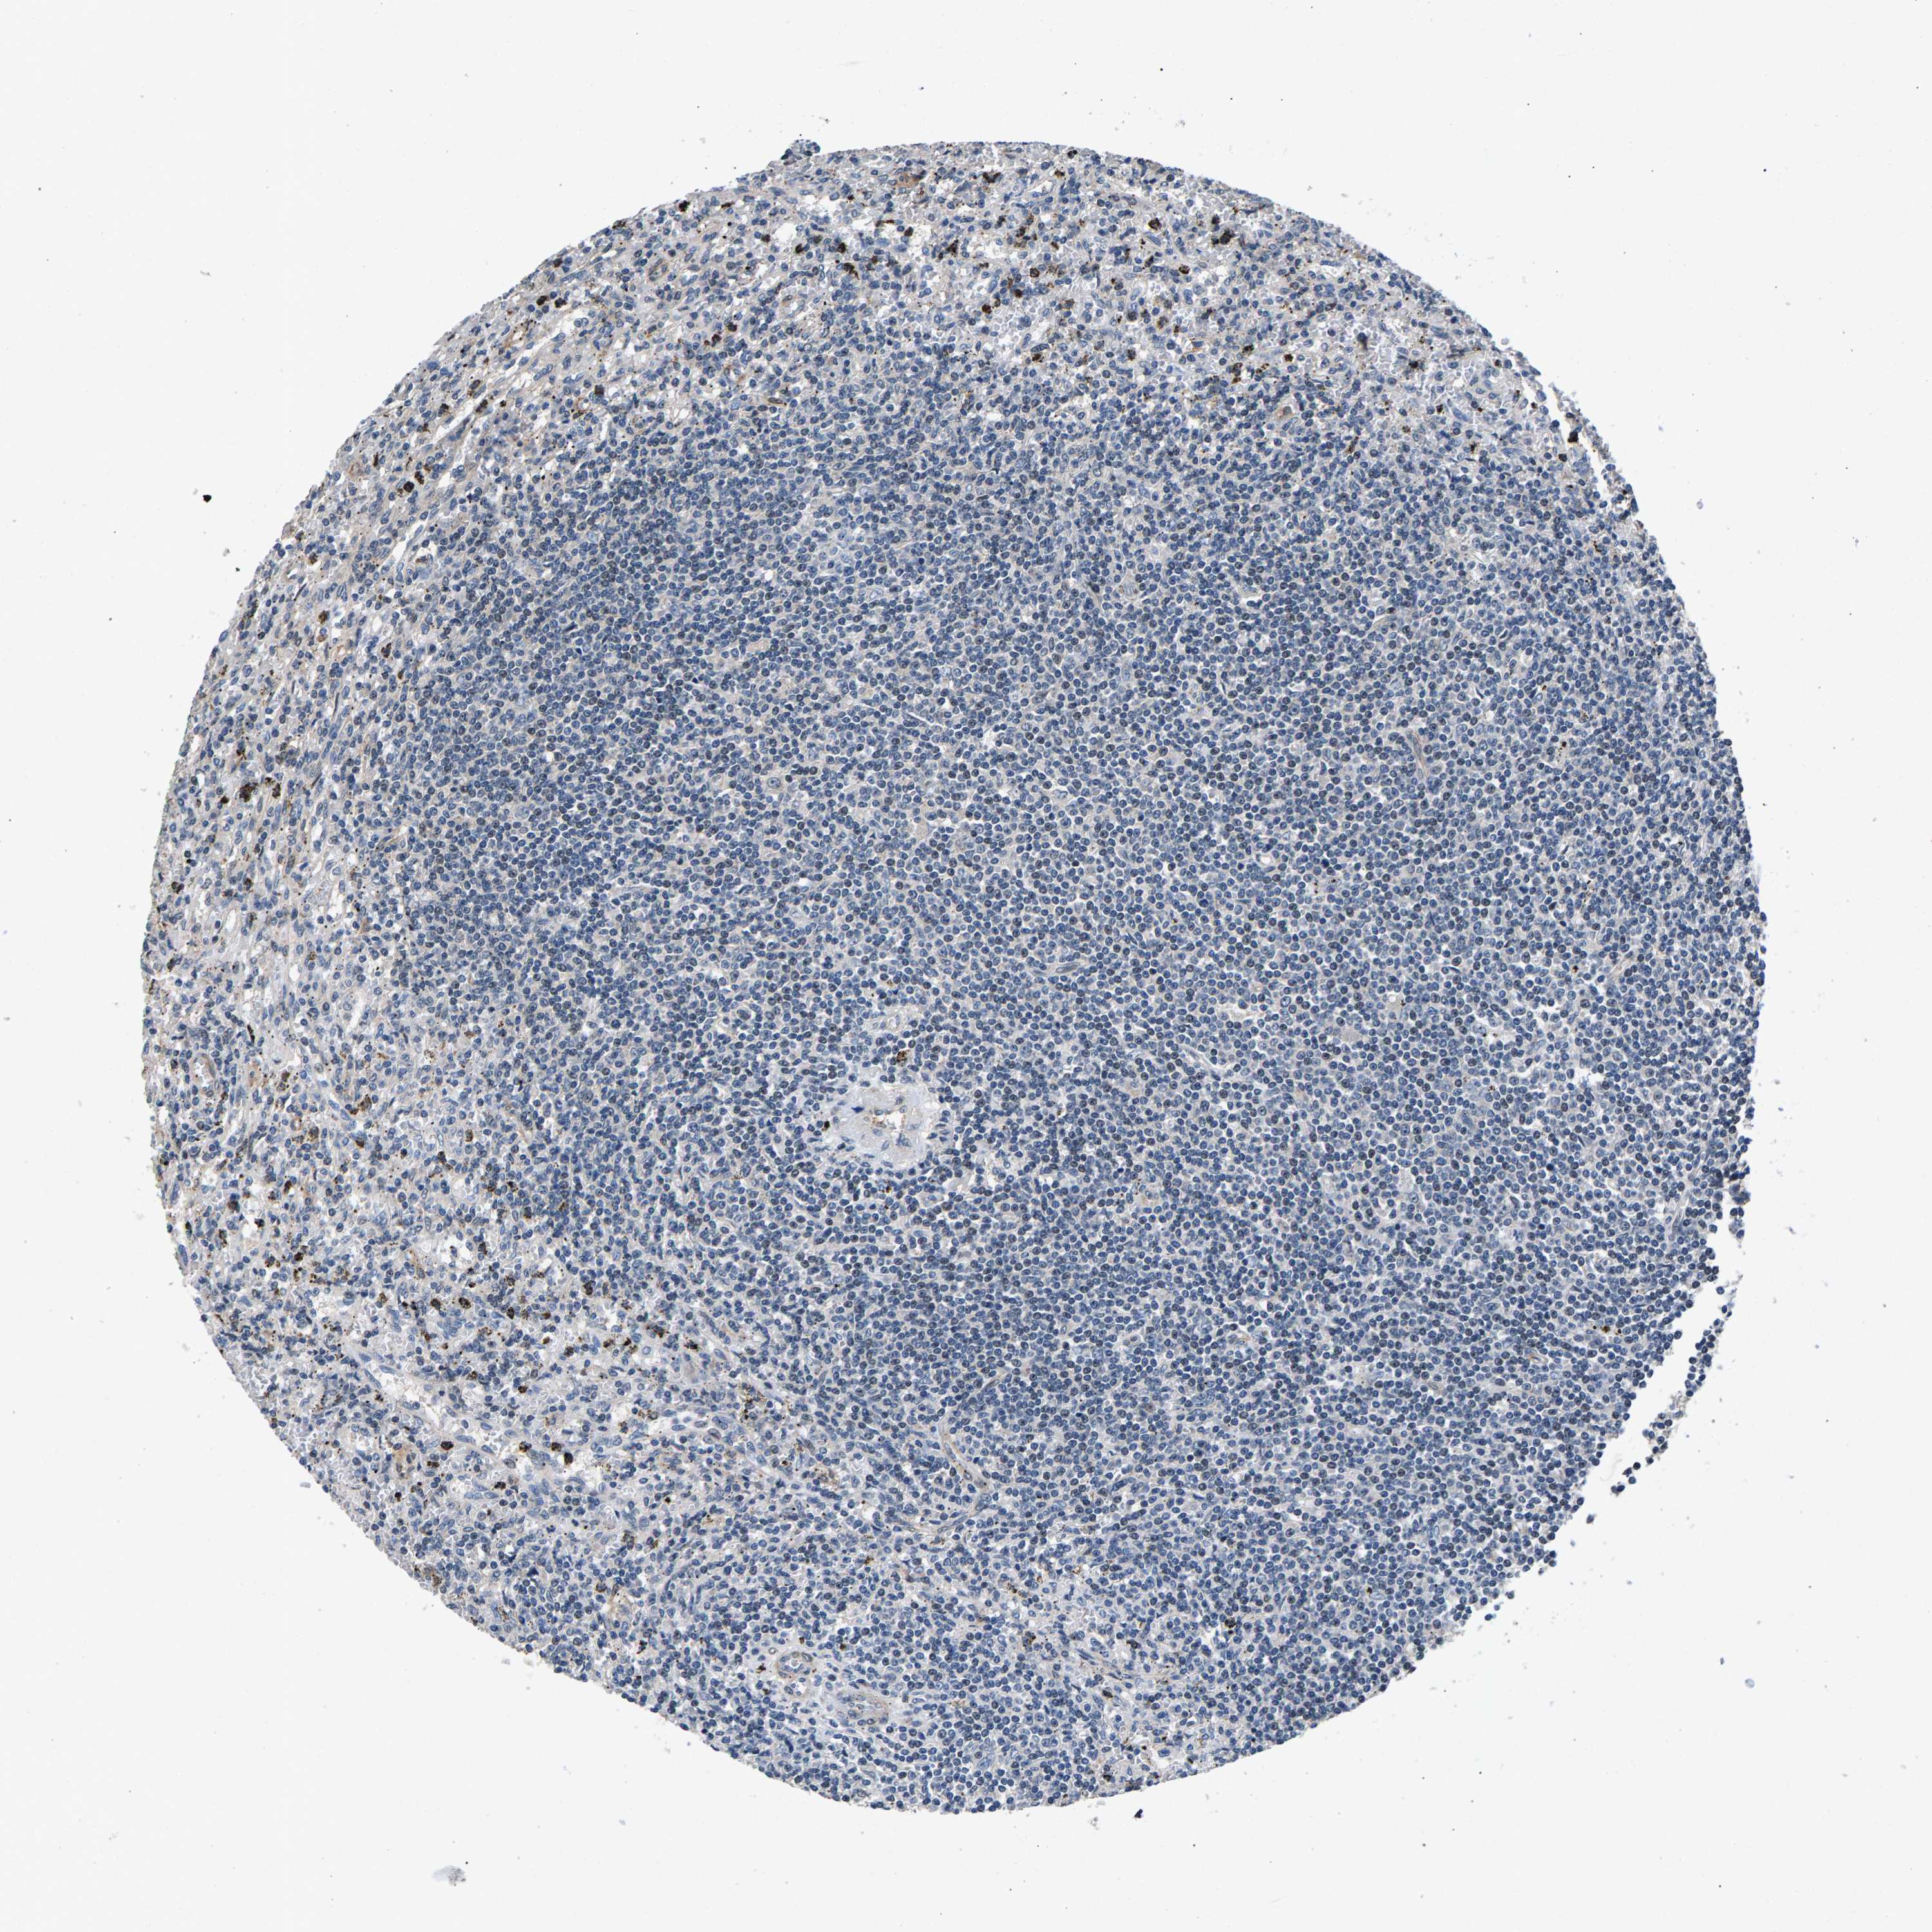

CANCER LYMPHOMA Show tissue menu

LYMPHOMA - Protein expressioni

A mouse-over function shows sample information and annotation data. Click on an image to view it in a full screen mode. Samples can be filtered based on level of antibody staining by selecting one or several of the following categories: high, medium, low and not detected. The assay and annotation is described here.

Each image is clickable and will lead to virtual microscopy that enables deeper exploration of all samples and also displays staining intensity scores, fraction scores and subcellular localization as well as patient and tissue information for each sample.

Antibody HPA019232

Antibody HPA021497

Antibody HPA021768

Hodgkin's disease, NOS

Malignant lymphoma, non-Hodgkin's type, High grade

Malignant lymphoma, non-Hodgkin's type, Low grade